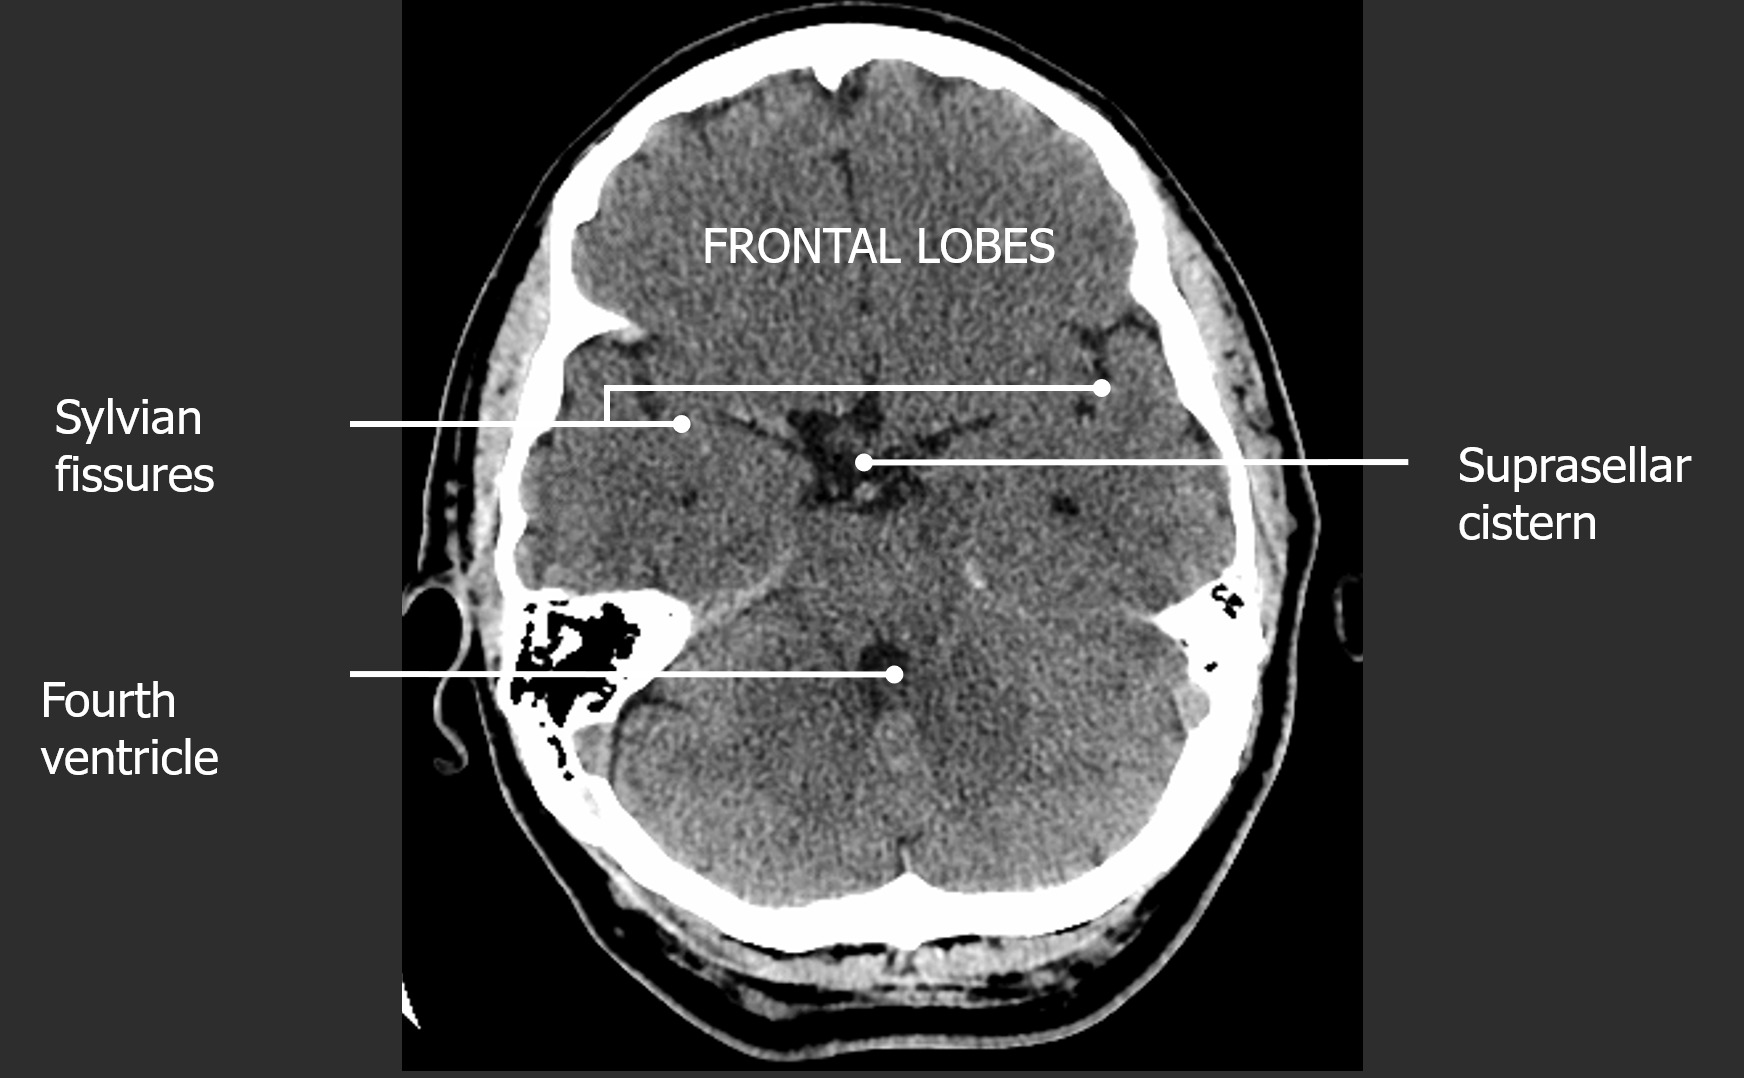

A tomografia computadorizada do crânio permite a avaliação detalhada das estruturas ósseas e das partes moles intracranianas. O conhecimento da anatomia em cortes axiais, coronais e sagitais é fundamental para a correta interpretação dos exames.

Figura 1: Cortes axiais de TC de crânio mostrando estruturas anatômicas principais

Fossa Posterior

- Tronco encefálico

- Cerebelo

- IV ventrículo

- Forame magno